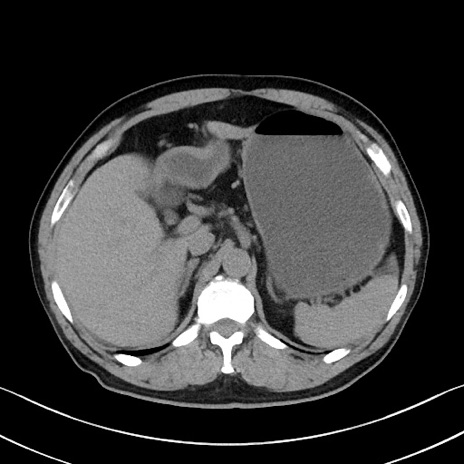

症例35(横断像)

【症例】70歳代 男性

【主訴】腹部膨満、嘔吐

【現病歴】昨日より腹部膨満感出現。本日増悪し、仙痛出現。嘔吐あり、受診。

【既往歴】糖尿病、胆摘後

【身体所見】BP 149/80mmHg、HR 74/min、BT 35.9℃、腹部:膨満、軟、圧痛なし。腸雑音減弱あり。上腹部正中切開瘢痕あり。

【データ】WBC 13500、CRP 1.72